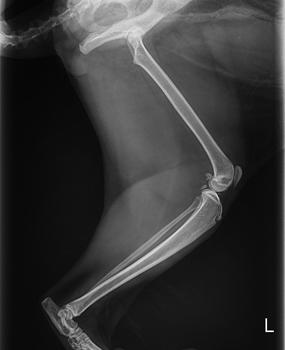

検査の結果 骨端軟骨形成と診断がつきました。

軟骨形成不全

正常

骨の成長に重要な「骨端軟骨」が正常に発達しないことで、骨や関節に異常が生じます。

特にレントゲン検査では、骨や関節の状態を詳しく確認することができ、

「どの関節に」「どの程度の変化が起きているのか」を正確に把握できます。